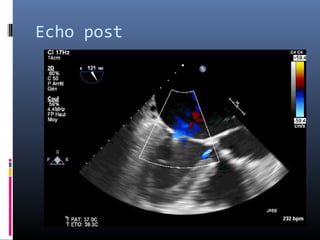

Echo post

Avant après